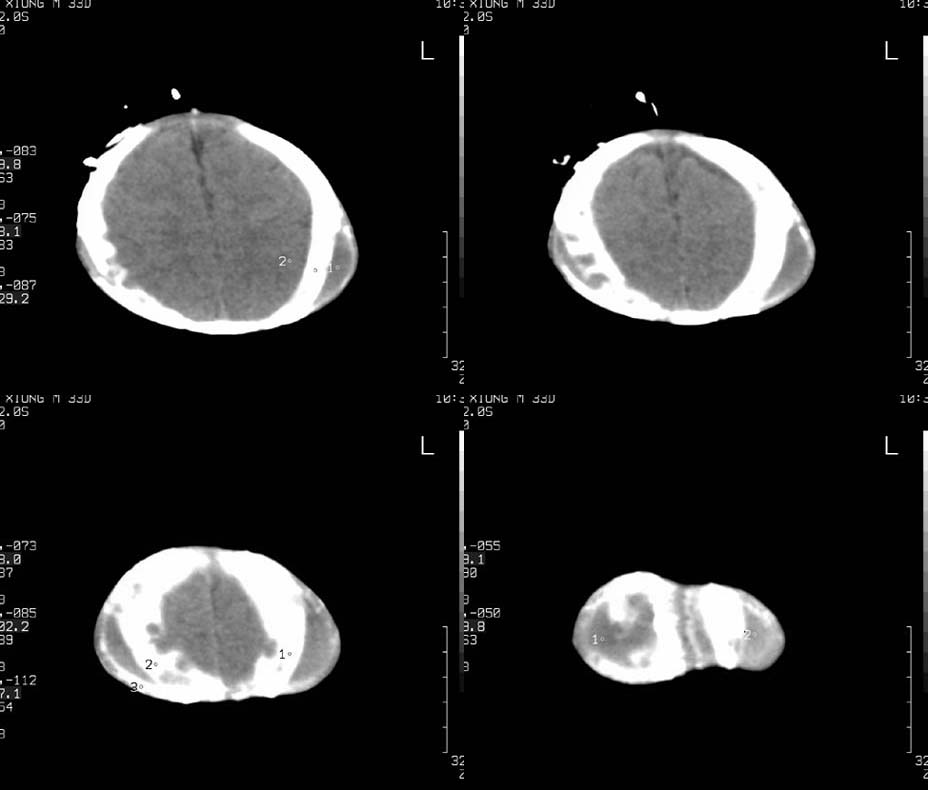

患儿,男,30天。出生时即发现两侧头顶部肿块,触诊似乒乓球样,其余各项检查未见异常。ct扫描:两侧顶骨外侧软组织密度影,ct值约29hu,脑皮质ct值约28.1hu。外缘尚见骨样结构。

典型双顶骨骨膜下血肿机化

双侧顶骨骨膜下血肿并机化钙化,我们医院经常见到,第一次碰到的时候还不知道是什么,后面见多了就不一样了,不过诊断应该与生产时情况结合。病史很重要。